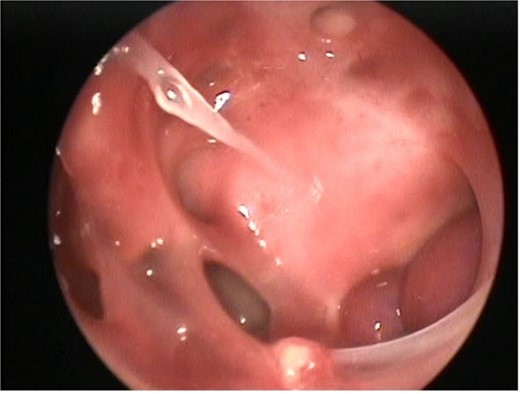

During surgery, the tumor was dissected from the pterygopalatine fossa using bipolar cautery. However, massive bleeding occurred from the tumor pedicle and the maxillary artery, which was controlled with repeated cauterization and packing of the nasal portion of the tumor. The sphenoid sinus was widely exposed by removing the posterior part of the bony septum. The tumor was then dissected from the sphenoid sinus, where further massive bleeding was encountered. This was successfully managed by applying Surgicel to the sphenoid sinus and pterygopalatine fossa. The postoperative endoscopic view of the left ICA within the left lateral sphenoid sinus is shown in Fig. 4.

Postoperative nasal endoscopy showing the left ICA within the left lateral sphenoid sinus.